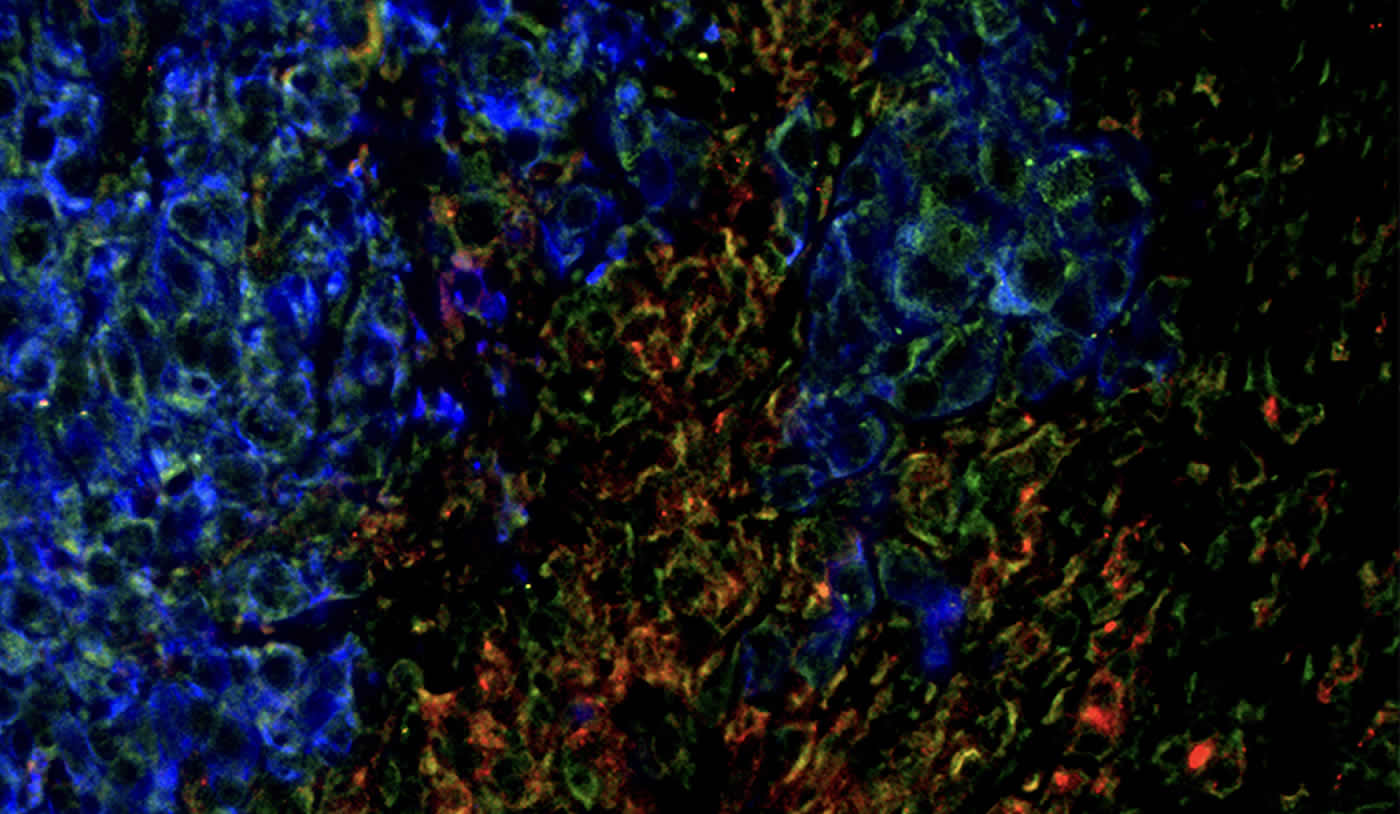

a brain slice from a patient with glioblastoma brain cancer

Brain CancerFeaturedGeneticsNeurology

·June 4, 2018·5 min read

A Potential Achilles Heel in Brain Cancer

A new study in PNAS reports blocking the expression of MDA-9/Syntenin forces glioma stem cells to lose their ability to induce protective autophagy.